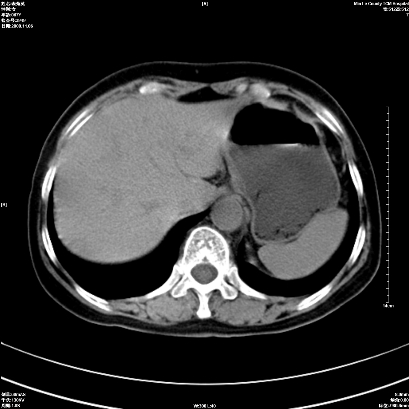

以下是引用卜一在2008-11-6 15:58:00的发言:[br]胰头略增大,胆总管扩张,末端渐行性狭窄。多考虑:胰头癌!建议增强!